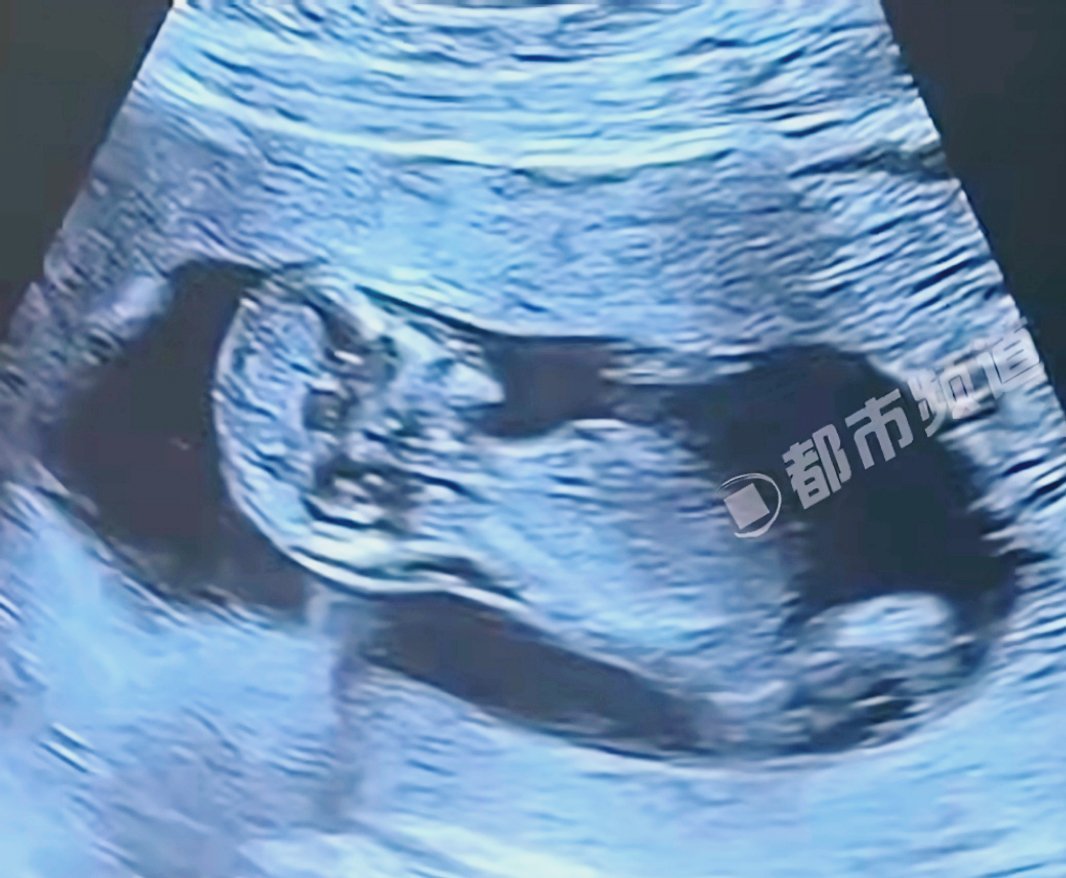

孕字提醒我们生命来之不易3000年前的孕期B超也太绝了孕字是一首无声的诗,吟唱着生命的奇迹与不易。它提醒我们,每一个新生命的到来都是一份来之不易的礼物。让我们怀着感恩之心,珍惜当下的每一刻。 ​​​